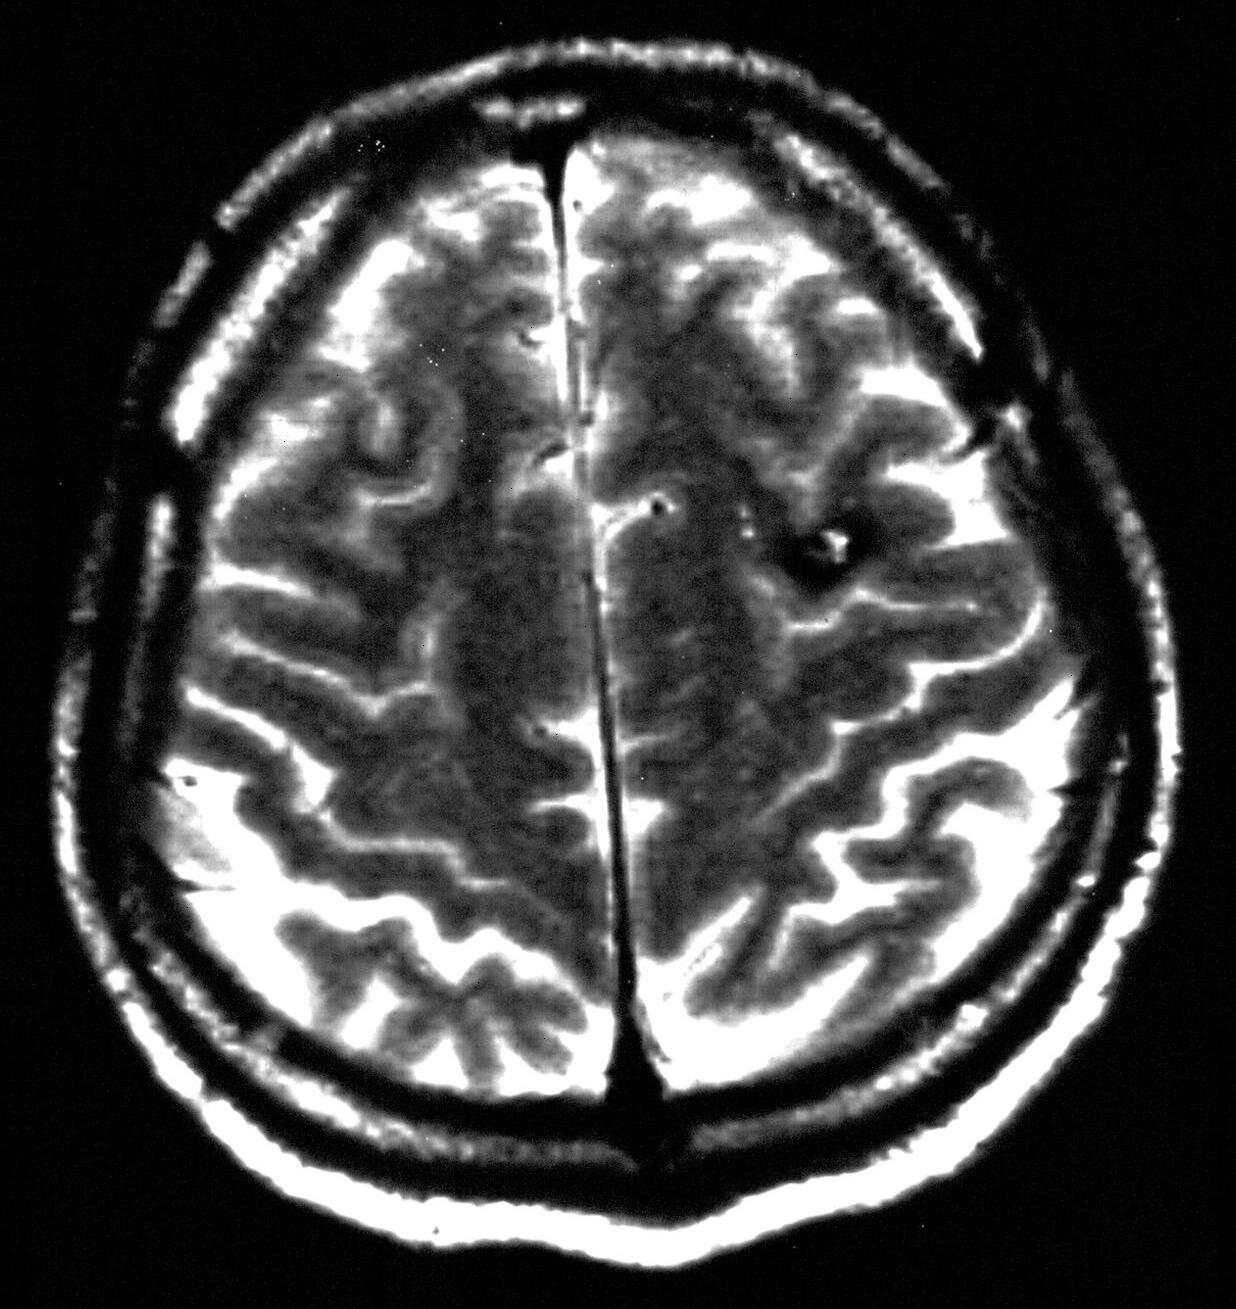

Obr.1.3 Chybnéurčenípolohyhemangiomuvzhledemksulcuscentralis

A: PředoperačníMRI:Frontálněvlevojuxtakortikálněložisko10×7mm. B: Operacebeznavigaceabezurčenízvratu fází.Připrvníoperacibylaprovedenapředsulcuscentralis,předv.precentralis,sulkotomieagyrotomie.Vhloubce3cm bylanalezenaširokážíla,jinakbylnáleznepřesvědčivý.Pooperacihemiparézavpravoaafázie.MRI:posteriorněodznáméhokavernomujsouprokrvácenépooperačnízměny.Podalšíoperacičástečnáapotřetíoperaciúplnáexstirpacekavernomu.Intracerebrálníhematom7×5cmfrontálněvlevo.Hemiplegievpravoaafázie.Dokladynejsouzpracovišťautorů.